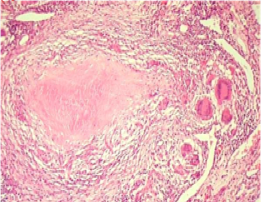

4、干酪性肺炎 干酪性肺炎可由浸润型肺结核恶化进展而来,也可由急、慢性空洞内的细菌经支气管播散所致。镜下主要为大片干酪样坏死灶。肺泡腔内有大量浆液纤维蛋白性渗出物。根据病灶范围的大小分小叶性和大叶性干酪性肺炎。此型结核病病情危重。

5、结核球 又称结核瘤(tuberculoma)。结核球是直径2-5cm,有纤维包裹的孤立的境界分明的干酪样坏死灶。多为单个,也可多个,常位于肺上叶。X片上有时很难与周围型肺癌相鉴别。结核球可来自:①浸润型肺结核的干酪样坏死灶纤维包裹;②结核空洞引流支气管阻塞,空洞由干酪样坏死物填充;或③多个结核病灶融合。结核球由于其纤维包膜的存在,抗痨药不易发挥作用,且有恶化进展的可能。X片上有时需与肺癌鉴别,因此临床上多采取手术切除。